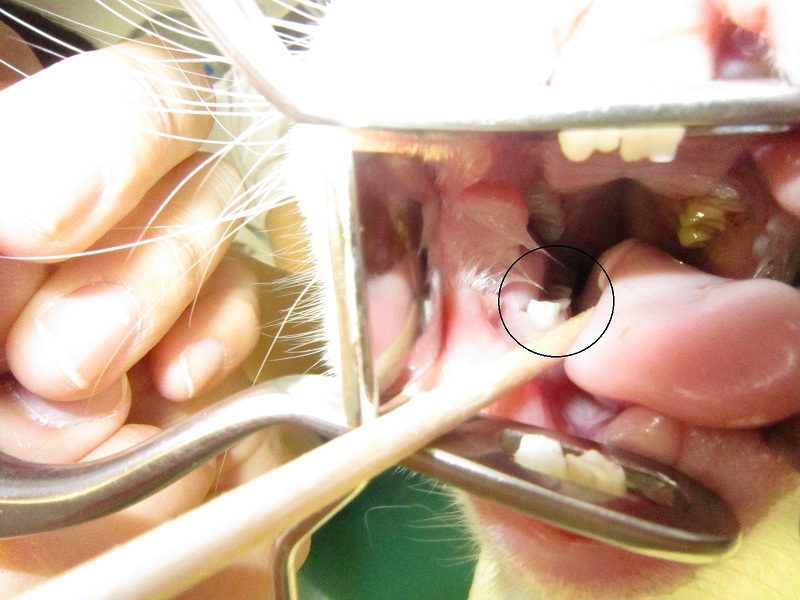

処置後 (2)

逆側の臼歯も丸く削りました。

これで舌にあたっても痛くありません。